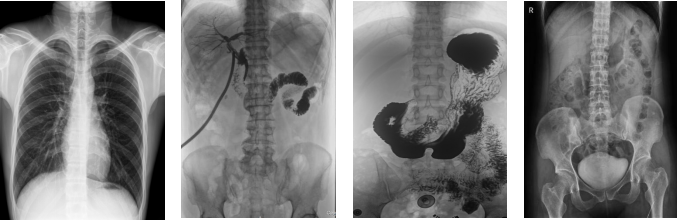

PLD8000C數(shù)字胃腸DR機(jī)臨床優(yōu)勢:

PLD8000C數(shù)字胃腸DR機(jī)全面突破傳統(tǒng)X射線攝影透視理念,成像部件采用新型動態(tài)平板探測器,輕松解決數(shù)字?jǐn)z影、數(shù)字透視、數(shù)字造影等功能,并使數(shù)字透視獲得超大尺寸和清晰的圖像效果。滿足放射科、體檢中心、影像中心、內(nèi)科、婦科、外科、急診科、骨科、創(chuàng)傷科、消化科等科室的各種臨床檢查需求。如果您想采購這款數(shù)字胃腸DR機(jī),歡迎咨詢400-025-6366。